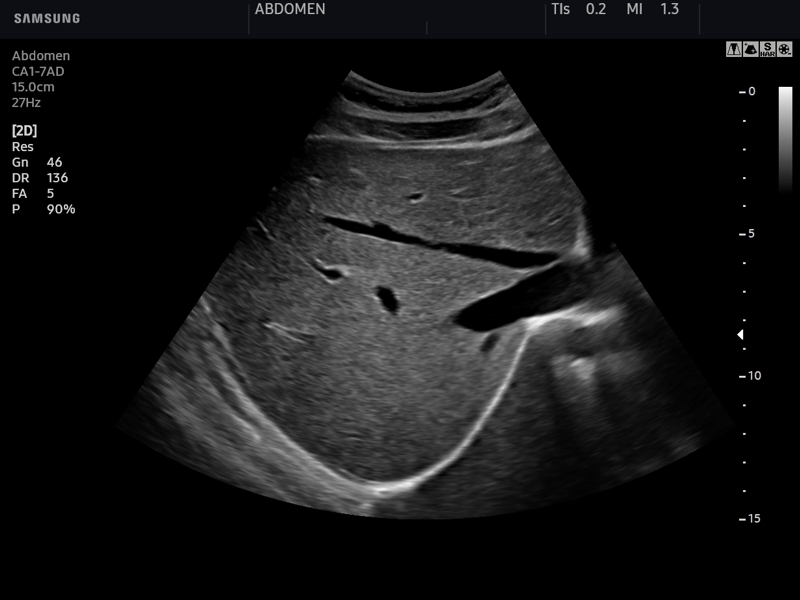

УЗИ печени может помочь диагностировать различные стадии гепатита С и цирроз печени. На мониторе видно, как выглядит печень, ее размеры, плотность, посторонние включения и прочие различные параметры органа. Каждое из заболеваний, в том числе гепатит С и его различные стадии, имеют свои особенные УЗИ-признаки.

УЗИ печени проводится ультразвуковым датчиком. Пациент должен лечь, задержать дыхание. В это время врач, проводя датчиком по животу, получает на экране монитора данные об исследуемом органе.

На экране в реальном времени отражается состояние печени исследуемого, ее структура, размер и прочие параметры. Чаще всего при исследовании печени используют ультразвук 2 D. Этот аппарат показывает на экране двухмерную, плоскую черно-белую картинку, которая имеет высоту и длину. В последнее время все более широкое распространение получают трехмерные аппараты ультразвука — 3D и 4D.